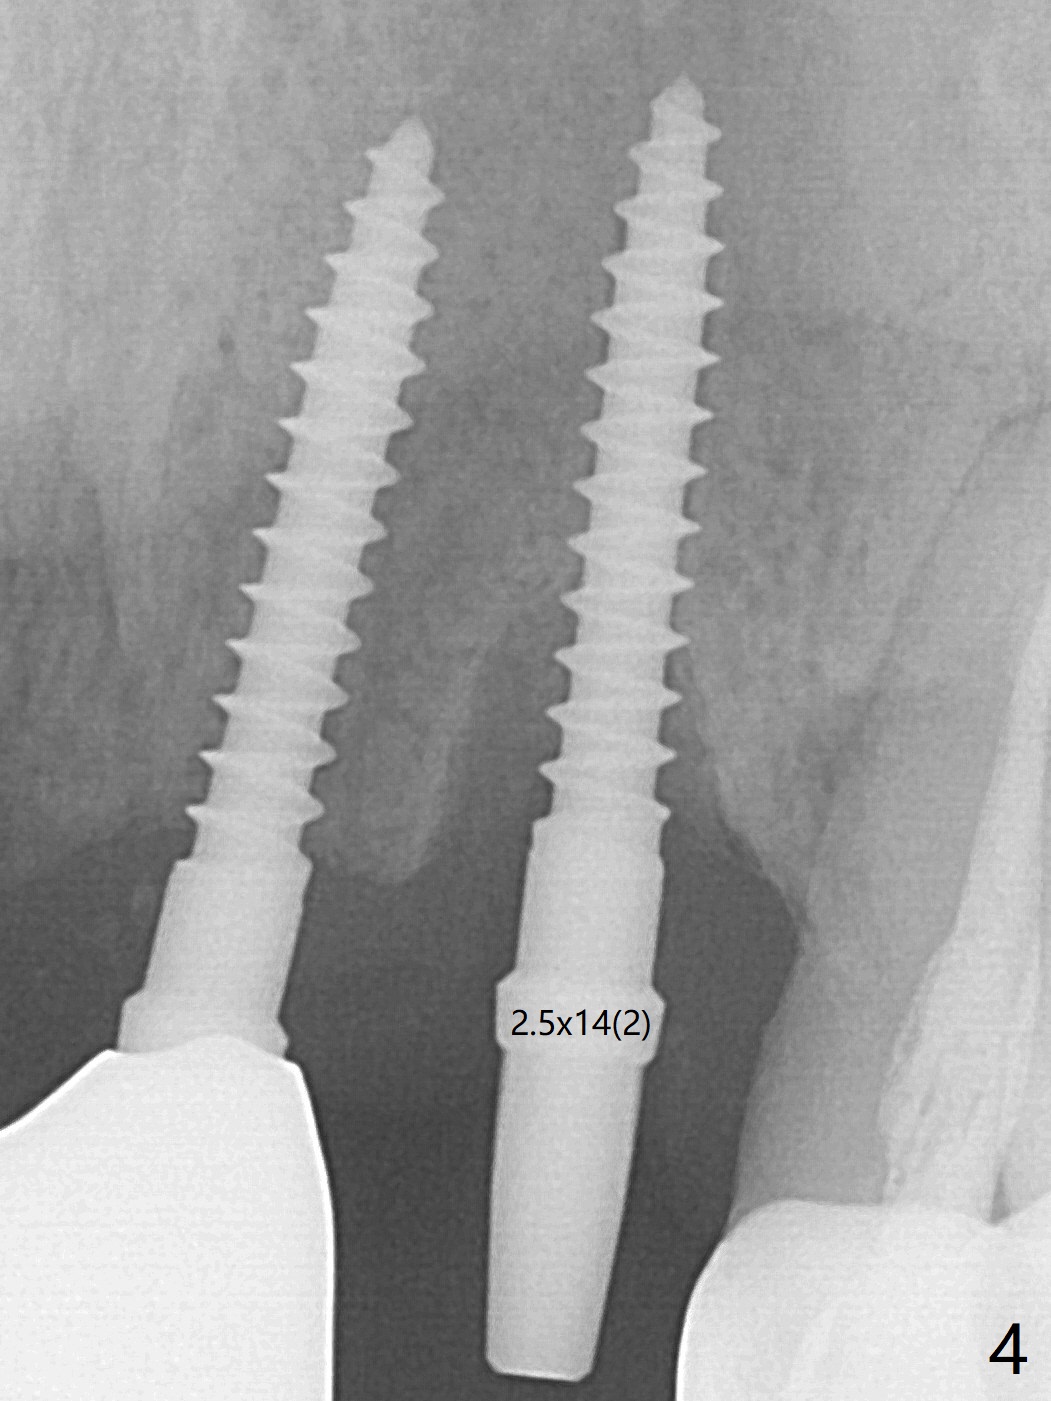

The tooth #10 has severe gingival recession (Fig.1) with loss of the buccal plate (Fig.2 *). After the initial osteotomy depth (Fig.3) increases by 2 mm, a 2.5x14(2) mm 1-piece implant is placed with insertion torque >60 Ncm (Fig.4). Palpation indicates the native bone apparently wider than CT shows. There is no sign of buccal or palatal plate perforation by palpation during osteotomy or implant placement. Vera Graft is placed repeatedly around the coronal threads (Fig.5-7 *). An immediate provisional is fabricated to close the socket (Fig.8). The buccal plate appears to collapse 1 month postop (cortical plate graft apparently more appropriate in this case); the margin of the provisional is trimmed so that the gingiva may grow incisally (Fig.9). The provisional dislodges several times postop due to short abutment. By nearly 4 months postop, the coronal bony defect seems to have been repaired (Fig.10 *). The tooth #11 has tenderness with bone loss (Fig.10 ^), corroborated by CT (distal bone loss, Fig.11 *). Since the apical bone is narrow (Fig.12), a narrow long implant is expected (Fig.13). Use an implant (3.5x13 mm) consistent with those at #14 and 15.